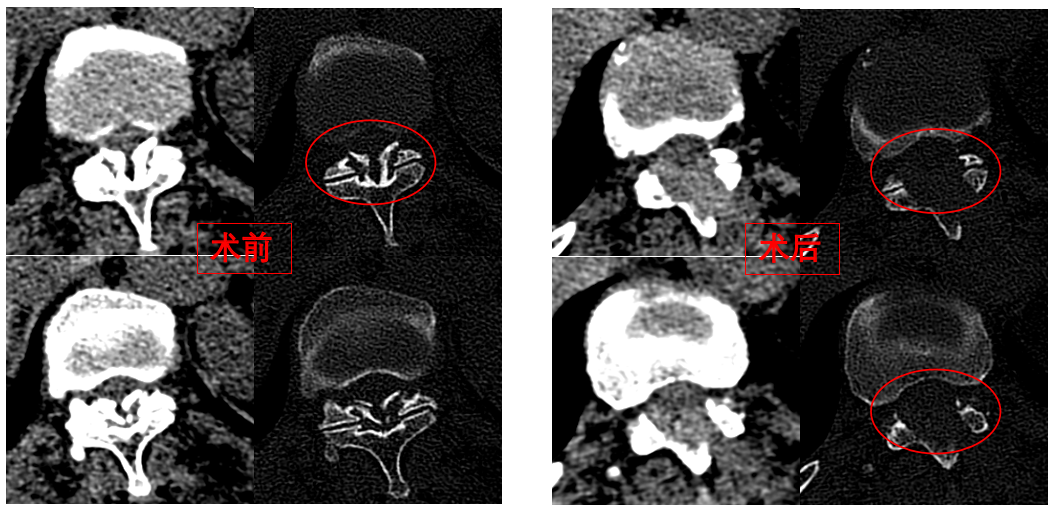

圖為卓瑪阿媽術(shù)前、術(shù)后胸椎CT照片對(duì)比。

華西醫(yī)院成辦分院骨科副主任醫(yī)師張斌接診后,憑借豐富的脊柱治療經(jīng)驗(yàn),立即安排卓瑪阿媽做了系列精密檢查,檢查結(jié)果顯示,阿媽胸椎11/12節(jié)段黃韌帶嚴(yán)重骨化,導(dǎo)致椎管顯著狹窄,脊髓受壓,確診為嚴(yán)重的“胸椎黃韌帶骨化癥”,如果不及時(shí)手術(shù)最終可能面臨癱瘓的風(fēng)險(xiǎn)。